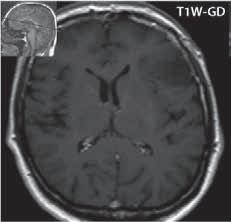

Základním cílem zobrazovacích metod je vyloučení ostatních, nenádorových, někdy expanzivních procesů (abscesu, vstřebávajícího se hematomu, různých typů cyst…), která mají zpravidla jiné klinické vedení. Při zobrazení nádorů bychom se měli snažit zodpovědět tři základní otázky, charakterizující tumor:

1. typing – odlišení nenádorových patologických procesů a snaha o histologickou klasifikaci tumoru.

2. staging – hodnotí stupeň pokročilosti růstu nádoru, kde kromě radiologického nálezu je nutné vzít v úvahu i neurologické a histologické vyšetření.

3. grading – určení stupně vyzrálosti nádoru, stupeň malignity (četnost mitóz, jaderná atypie, angiogeneze, nekrózy).

Základní rozdělení nádorů je intraaxiální (vycházející z mozkové tkáně), např. astrocytom, oligodendrogliom, ependymom…a nádory extraaxiální mající původ v tkáních okolních – např. meningeom, adenom hypofýzy… Dalším možným členěním je na nádory primární a sekundární, resp. mozkové metastázy nebo tumory supratentoriální a infratentoriální. Rozlišení na nádory maligní a benigní nemá vždy ostrou hranici, a proto histologové určují stupně malignity I.–IV. (WHO 2007).

Vzhledem k pokrokům v diagnostickém zobrazování se daří zlepšovat substrátovou diagnostiku. Například u gliomů nedávné práce ukázaly, že nález na ADC mapě může pomoci při odlišení nádorů s vyšším stupněm malignity, je zde nižší hodnota než u gliomů s nižším stupněm malignity (u maligních je vyšší buněčnost, tedy pokles difuzivity). Jiné práce se zabývaly perfuzí a ukázaly, že k odlišení pomáhá rCBV (zvýšené u vyššího gradingu tumorů), především na odlišení II. a IV. či III. a IV. stupně. Jako nejvýtěžnější se jeví pro jejich diferenciaci užití kombinace ADC mapy s rCBV.